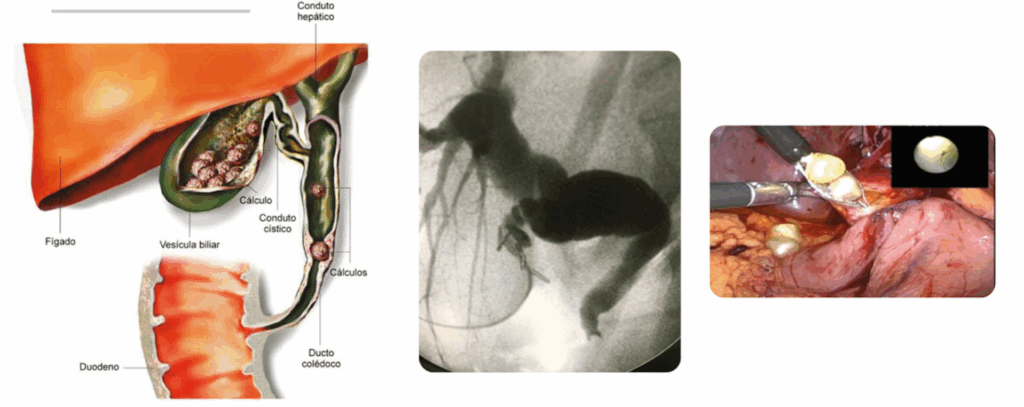

Segundo a literatura médica cerca de 5% dos pacientes com colelitíase (pedra na vesícula biliar) podem ser acometidos por uma patologia chamada de coledocolitíase (figura 1), que é quando um ou mais cálculos deslocam-se do interior da vesícula e vão se alojar no canal do fígado, esse canal é chamado de colédoco ou via biliar principal. Podendo o paciente desenvolver icterícia (ficar com pele e olhos amarelados), a urina pode ficar escura e as fezes claras, e caso não seja tratado pode ocorrer colangite que é a infecção dos canais do fígado (vias biliares). Mas em alguns casos o diagnóstico do cálculo no canal do fígado só é realizado durante a cirurgia de retirada da vesícula, através de um exame que injeta contraste na via biliar e realiza uma imagem de raio X, chamada de colangiografia (figura 2).

- Tratamento por videolaparoscopia, explorando o colédoco para retirada de cálculos através de uma segunda microcâmera que entra nesse canal e retira da vesícula no mesmo ato cirúrgico (figura 3).

O tipo de tratamento para cada caso é muito específico e depende de muitas variáveis como a condição clínica do paciente, o tamanho do cálculo, o grau de infecção das vias biliares (colangite), e se os cálculos estão nos canais internos do fígado (necessitando algumas vezes de retirar uma parte do fígado), a disponibilidade de equipamentos e médicos cirurgiões endoscopistas com experiência. Na rotina dos últimos estudos demonstraram menor tempo de internação, em casos selecionados, é a exploração laparoscópica (por vídeo) do colédoco no canal do fígado e retirada da vesícula biliar no mesmo procedimento (figura 3), porém necessita de aparelhos especializados e cirurgiões experientes em vias biliares e laparoscopia.